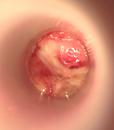

Inflammation aigüe de la muqueuse rectale

Symptomatologie variable : parfois pauci-symptomatique (quelques rectorragies d’allure canalaire) jusqu’à parfois très bruyante (véritable syndrome rectal avec ténesme, épreintes, faux besoins et diarrhée glairo-sanglante, pouvant être associé à des douleurs abdominales)

Etiologies : infectieuses (principalement IST type chlamydiose, gonococcie ; plus rarement Clostridium difficile, amibiase, CMV, tuberculose …), inflammatoires (MICI), traumatiques, ischémiques, iatrogènes (lavement…)